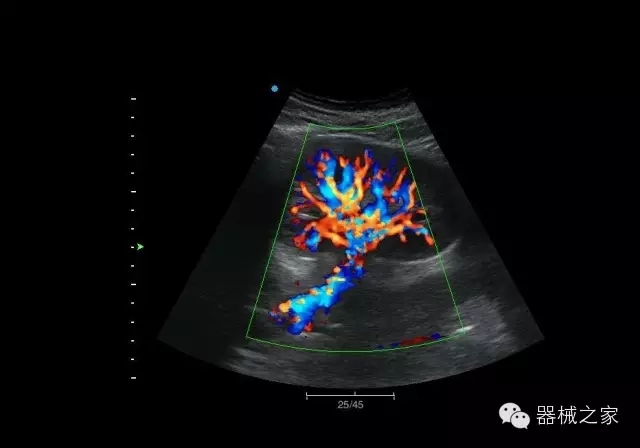

經(jīng)典產(chǎn)品:Apogee 1000

臨床圖片賞析

結(jié)甲

腎臟血流

肝血管瘤

產(chǎn)品特點(diǎn)

·屏幕可左右90度旋轉(zhuǎn);

·雙模操控;

·兩用提手;

·雙鋰電池;

·超輕機(jī)身;

·15寸高亮高清醫(yī)學(xué)顯示器;

·衛(wèi)星布局操控面板;

·一體化剪切板;

·多功能導(dǎo)航鍵;

“宏云”平臺(tái)

·采用移植自高端臺(tái)式彩超的“宏云”平臺(tái)技術(shù),使系統(tǒng)具有更優(yōu)秀的圖像效果;

人性化的設(shè)計(jì)

·內(nèi)置電池,輕巧的外觀設(shè)計(jì)以及臨床功能、軟硬件設(shè)計(jì)的人性化設(shè)計(jì),使系統(tǒng)在臨床多科室移動(dòng)診查中,均從容應(yīng)對(duì);

Fusion THI二代融合諧波成像

·在不同諧波頻率段獲得的信息進(jìn)行實(shí)時(shí)融合,既能獲得諧波圖像分辨率又能提高圖像的穿透力,降低圖像噪音;

XBeam多域復(fù)合成像

·通過頻域和空域角度進(jìn)行復(fù)合的圖像處理,能有效消除由于圖像離散化和圖像衰減引起的空間分辨率下降的不利影響,彌補(bǔ)原有圖像空間分辨率的不足,獲得更加清晰的圖像;